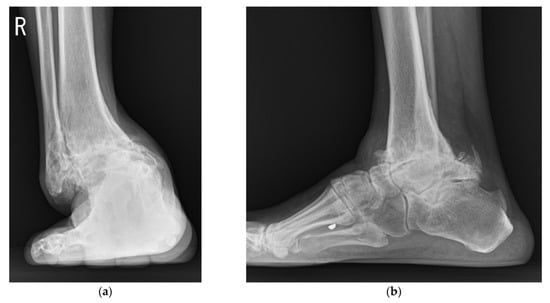

Union was obtained in all cases without additional surgery. The pre- and postoperative radiographic results are shown in Table 1. A total of 15 ankles (41.7%) had talar tilt of more than 15°, and 10 ankles (27.8%) had talar center migration of more than 8 mm in the coronal plane preoperatively (Figure 10). Eight ankles (22.2%) had an anteroposterior offset of more than 10 mm preoperatively. Talus center migration (p = 0.001), sagittal talar migration (p < 0.001), and hindfoot alignment angle (p = 0.001) significantly improved after surgery (Figure 11).

Figure 11. Postoperative weightbearing radiographs taken at 1 year after surgery showed union with improved position: (a) anteroposterior view; (b) lateral view.